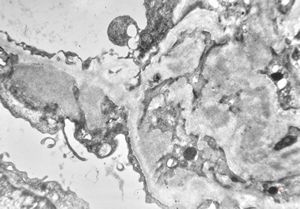

M,29y. | type II membranoproliferative glomerulonephritis (dense deposit disease)